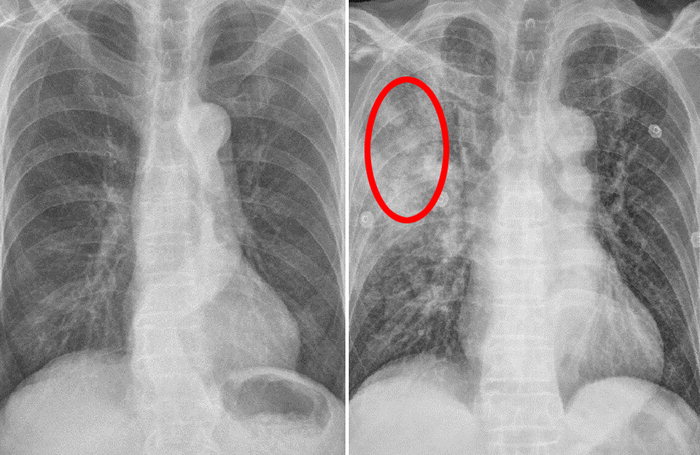

호흡 곤란

호흡 곤란은 폐암의 증상입니다. 폐암 환자의 약 4분의 1이 호흡곤란 증상을 보이며, 이는 다발성 폐 전이가 양측 증상을 나타내거나 악성 흉막삼출이 폐암과 함께 발생할 때 발생합니다. 폐암은 점차 흉통을 악화시킬 수 있으며, 폐암이 진행됨에 따라 폐암의 크기가 커지거나 그 부위에 물이 차게 되면 호흡이 흉막을 자극하여 호흡곤란과 흉통을 유발할 수 있습니다. 격렬한 작업이나 격렬한 운동을 하지 않았더라도 호흡곤란이 발생하거나 호흡이 불편한 경우 의사의 진찰을 받는 것이 좋습니다.

가슴 통증

폐암의 초기증상 중에 흉통이 있습니다. 폐암 환자의 약 1/3이 흉통을 호소합니다. 흉통의 원인은 폐 가장자리에 종양이 형성되어 암세포를 생성하고 흉벽과 흉막에 침착되어 통증을 유발하는 것입니다.

흉통의 원인은 여러 가지가 있을 수 있지만, 오늘날 우리가 다루고 있는 폐암으로 인한 흉통은 경미한 통증보다는 지속적인 따끔거림과 둔한 통증을 동반한다는 점에 유의하시기 바랍니다. 또한 암은 흉막이나 흉벽 대신 갈비뼈로 퍼져 통증을 유발할 수 있습니다. 종양은 주변 조직 세포를 자극할 수 있으므로 계속해서 통증을 유발하는 경우 의사의 진찰을 받는 것이 좋습니다.